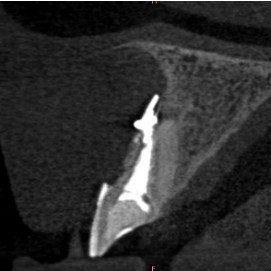

Pacjentka lat 72, od kilkudziesięciu lat chorująca na cukrzyce I typu, obecnie od 10 lat na pompie insulinowej. Profesor medycyny, siostrzenica pacjentki prowadzi swoją ciocię diabetologicznie, pacjentka świadoma zagrożeń przy zabiegach regeneracji kości i implantacji w takim ogólnym stanie zdrowia. Po rekonstrukcji tkanek miękkich i kości osadzono dwa implanty o średnicy 5,0 mm. Na zdjęciu śródzabiegowym widać zadowalające wyniki rekonstrukcji tkanki kostnej. Po upływie kilku miesięcy wykonano nadbudowę protetyczną.